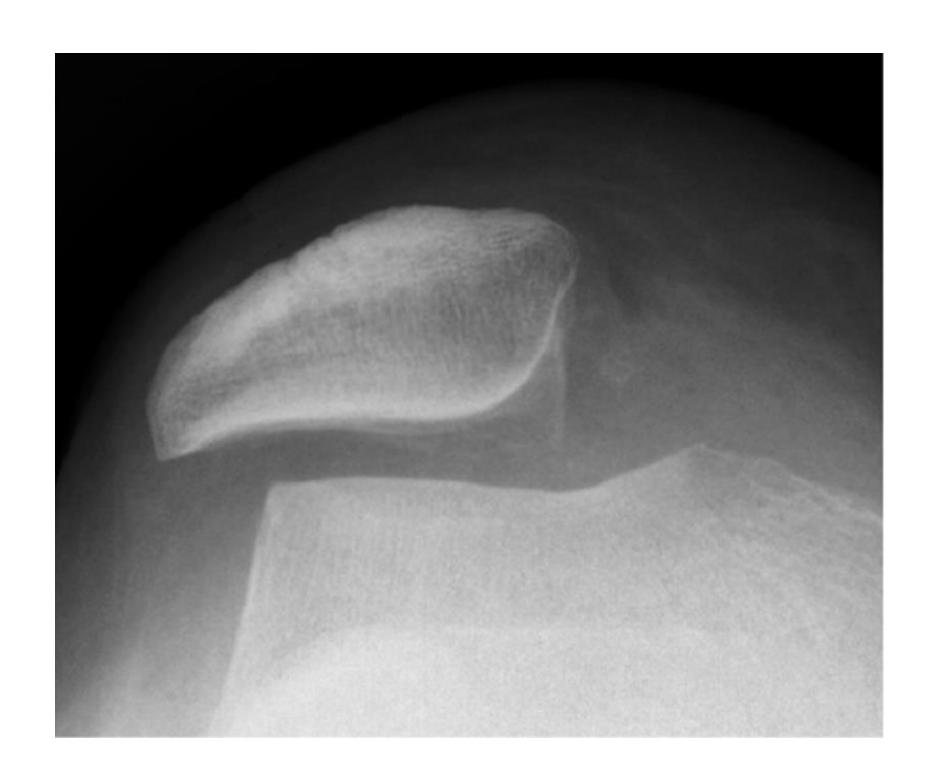

Hill-Sachs Lesion

What does this photo show?

- Hill-Sachs lesion

18-year-old male presented after sport injury and unable to do internal rotation of right shoulder. What is the name of the injury seen in the figure?

- Hill-Sachโs defect

18-year-old male presented after sport injury and unable to internally rotate his left shoulder. What is the diagnosis?

A case scenario about a male with anterior shoulder dislocation. What does the figure 1b show?

reverse - Hill sachs lesion

What do you see in this image?

- Hill sachs lesion